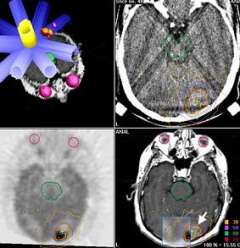

Stereotactic radiosurgery: The upper left image shows a treatment plan in which beams of radiation (in blue) are all directed at a tumor target at various angles around an arc. The diameter of each beam is based on the cross-sectional size of the tumor from that direction. Note that certain radiation sensitive structures do not have radiation passing through them, including the brainstem (green) and eyes (lavender). The other three images (upper right, CT; lower left, PET; and lower right, MRI), show how UCLA doctors can use imaging information from many different types of advanced diagnostic imaging machines for the best treatment planning of this target (arrow).